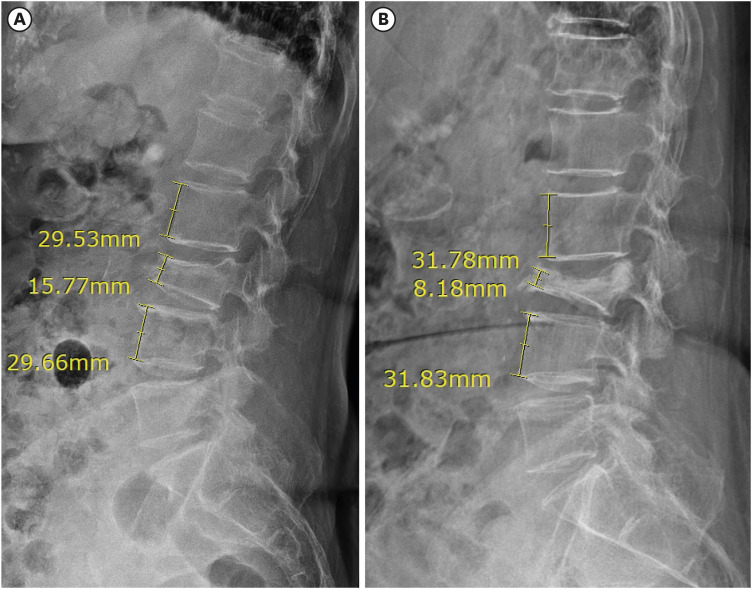

Methods: A total of 122 patients with OVCF, who were follow-up duration > 6 months, were included. Factors, such as age, sex, fracture levels, bone mineral density, body mass index, medications for osteoporosis, initial compression rate, fracture locations, and pelvic incidence were assessed. The compression rates were measured initially and at 1, 2, 3, and 6 months. The correlation between these factors and compression rate progression of > 50% was analyzed using univariate and multivariate Cox regression analyses. The compression rate progression over time was evaluated using a repeated-measures general linear model, and clinical outcomes were assessed using a paired t-test.